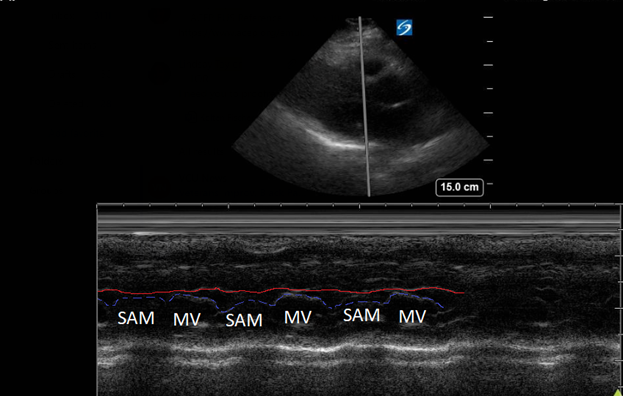

A point-of-care ultrasound was performed to evaluate for potential etiologies of syncope. The ultrasound displayed biventricular and interventricular septal hypertrophy (Figure 2), systolic anterior motion of the mitral valve (SAM, Figure 3), and a “dagger-like” continuous wave Doppler waveform emerging from the left ventricular outflow tract. (LVOT, Figure 4)

Figure 3. Parasternal long-axis view using M-Mode displaying SAM of the mitral valve against the interventricular septum (red line). Note how the mitral valve shifts anteriorly during the same period that the septum contracts posteriorly.

Hypertrophic obstructive cardiomyopathy (HOCM) refers to the common obstructive subset that affects 70% of patients with HCM.6 Left ventricular outflow tract obstruction (LVOTO) has been shown to be an independent predictor for adverse outcomes by multiple studies.7 Traditionally, systolic anterior motion (SAM) of the mitral valve was thought to be pathognomonic for HCM. Recent studies have shown that of the HCM patients with SAM, 25-50% will have LVOTO.8 Using ultrasound, SAM is observed in the parasternal long-axis using M-mode over the anterior leaflet of the mitral valve. The time the valve is contact with the septum quantifies disease severity.

1) Mild: brief SAM without septal contact

2) Moderate: septal contact < 1/3 of systolic period

3) Severe: septal contact > 1/3 of systolic period9